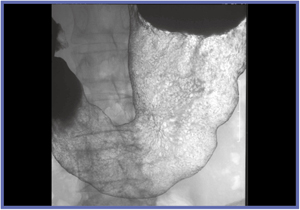

FPD装置1号機は,透視が見えにくい状態で撮影されたが,非常に精細な画像を得ることができた(図1,2)。偶然にも被検者が胃がんUc(表面陥凹)であったことも,評価を行う上で良い条件となった。1号機の評価は,非常にきれいに写るの一言に尽きる。透視が難しいことが大きな課題となっていたが,98年に現在の透視技術の完成に至った。

![]() 図1 FPD装置1号機の撮影像 わずかな表面陥凹が確認できる。 |